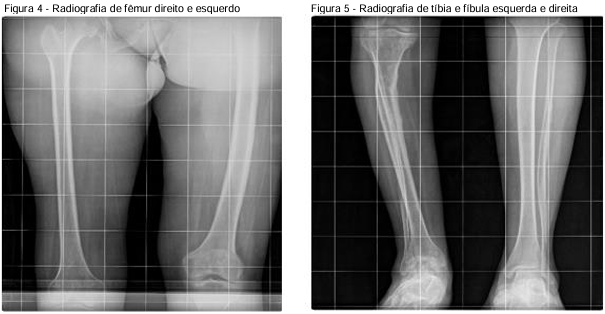

Em radiografia panorâmica de membros inferiores e escanometria apresenta os seguintes resultados: Textura óssea reduzida, notadamente a direita; Afilamento do fêmur, tíbia e fíbula a direita; Encurvamento da diáfise da tíbia direita; Avançadas alterações degenerativas do tornozelo a direita; Hipotrofia da musculatura a direita e Infradesnivelamento da asa ilíaca direita em cerca de 6 cm (Figuras 4, 5 e 6).

Fonte: Prontuário médico (2024)